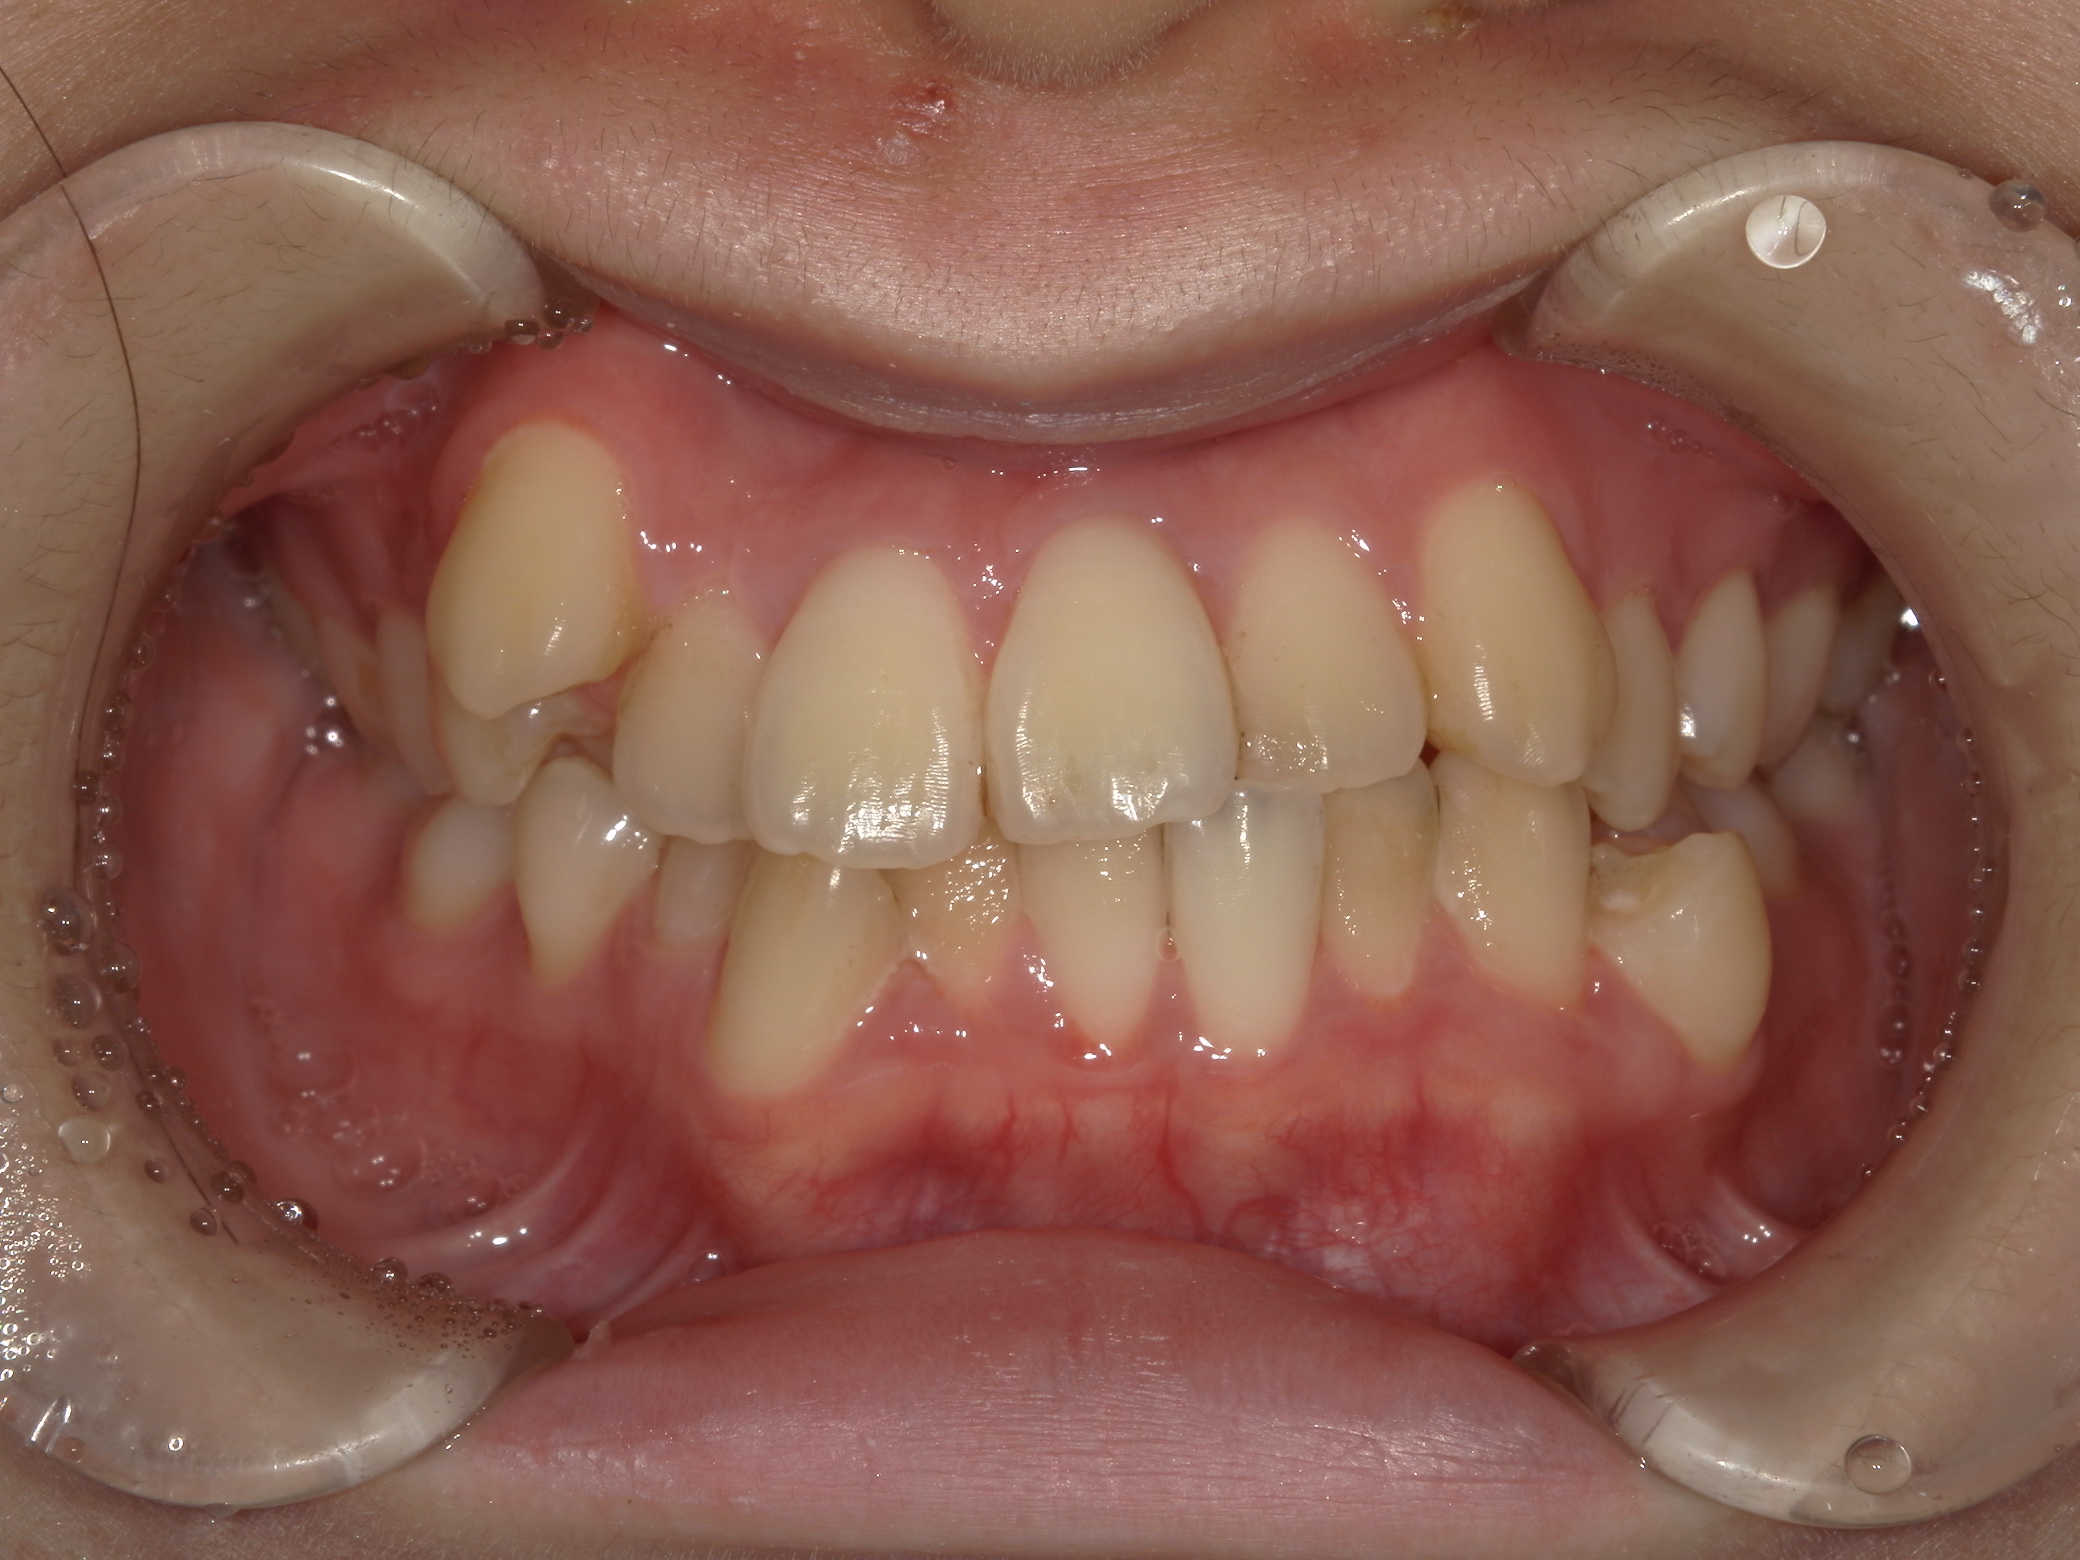

歯並び・かみ合わせ・口元の見た目が気になる

| 年齢・性別 | – |

|---|---|

| 主訴 | 歯並び・かみ合わせ・口元の見た目が気になるとの事でご相談があり矯正の治療を行いました。 |

| 治療期間・回数 | 2年 |

| 費用 | 1,001,000円 |